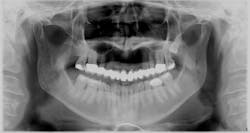

Pretreatment bitewings

Next came the comprehensive evaluation by the dentist, which was just as extensive. Her existing bridge from Nos. 3 to 14 had fractured porcelain, recurrent decay on No. 4 mesial, No. 5 distal, No. 12 distal, No. 13 mesial and distal, and No. 14 mesial. Additionally, decay was noted on No. 18 buccal and No. 20 distocclusal.